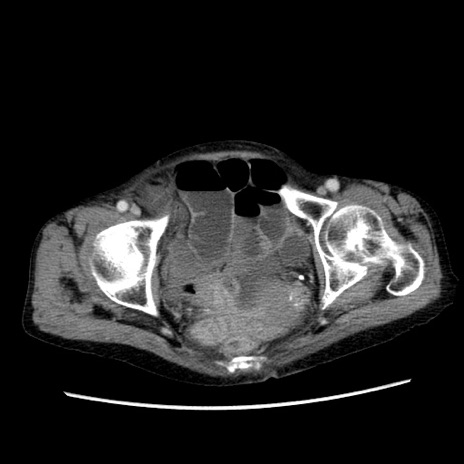

症例25(横断像)

【症例】80歳代女性

【主訴】胸のつかえ感

【現病歴】約9時間前に食後から胸のつかえた感じあり、嘔吐あり、来院。

【既往歴】胃癌(全摘)、胆摘、虫垂炎

【身体所見】心窩部に圧痛あり、反跳痛なし。

【データ】WBC 5700、CRP 0.05